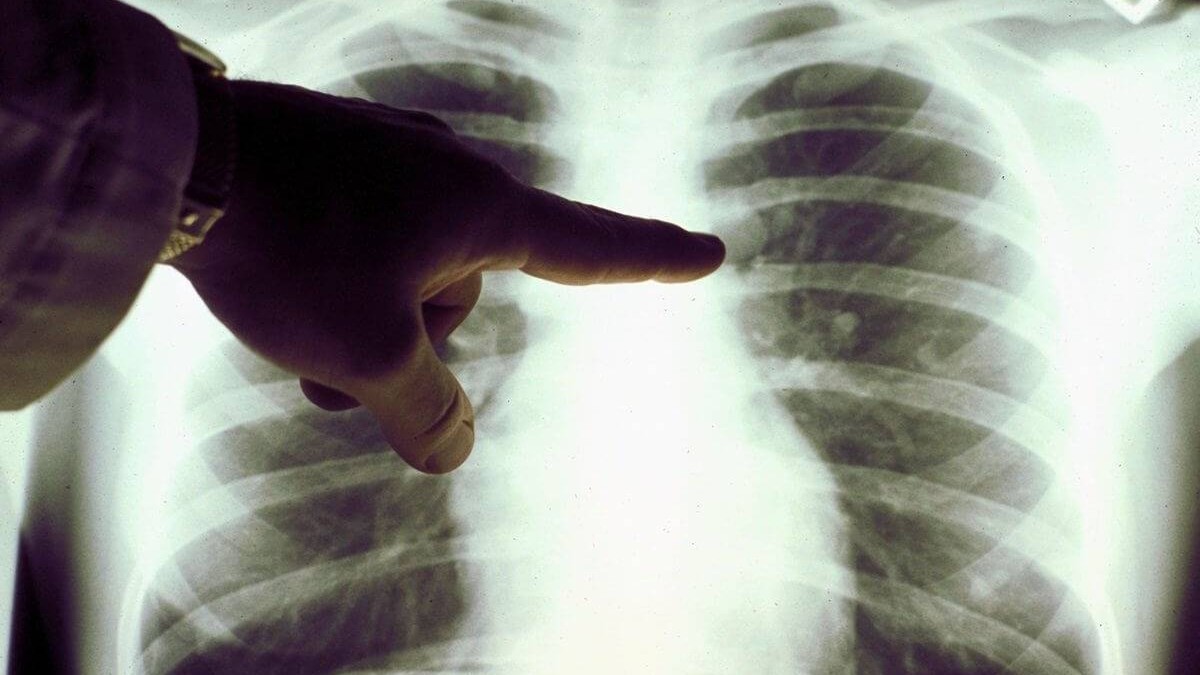

Күніне Қазақстанда пневмониямен 2,5 мың адам ауырады - Денсаулық сақтау министрлігі

Жаңа денсаулық сақтау министрі Алексей Цой коронавирустың таралуына қарсы күрес шаралары жөніндегі кеңесте Қазақстанда күніне 2,5 мыңға дейін пневмония ауруы тіркелетінін айтты.

«10 маусымнан бастап біз COVID-19 клиникасында пневмонияның едәуір өсуін және ПТР теріс нәтижесін көрдік. Соңғы күндері күніне 2,5 мың жаңа пневмония тіркелді», - деді Цой.

Бұған дейін Қазақстанның кейбір аймақтарында пневмониямен ауыратындардың саны күрт өскені туралы хабарланған болатын .

Пневмонияны қалай тануға болатындығы туралы Денсаулық сақтау министрлігінде айтылды

С.Асфендияров атындағы ҚазҰМУ жұқпалы және тропикалық аурулар кафедрасының профессоры, м.ғ.д. Равиля Егембердиева пневмонияның коронавирус фонында болатынын түсіндірді. Оның айтуынша, пневмония - коронавирустық инфекцияның көрінісі және оны бөлісуге болмайды. «Яғни, инфекция жоғарғы тыныс жолдарынан, мұрын-ішек жолынан, трахеядан, бронхтан өтіп, өкпеге жетті. Сонымен қатар қабыну процесі жүреді. Бұл пневмонияның табиғатын зерттеу керек, пациентті ПТР тексеріп, бүкіл тарихты жинау керек. Бұл коронавирустық этиологияның пневмониясы. », - дейді профессор Егембердиева.